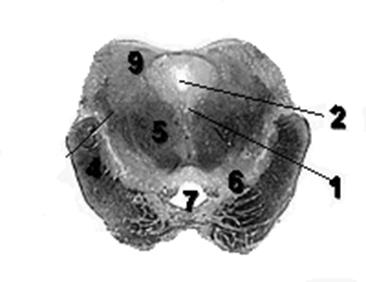

На поперечном срезе, проведенном через оливы (oliva) (см. рис. 1), в последних различают скопления серого вещества. Наибольшее из них, нижнее оливное (nucleusolivarisinferior) или зубчатое ядро (nucleusdentatus), имеет складчатую форму. Также в оливах можно различить ядра меньшего размера: медиальное добавочное ядро оливы (nucleusolivarisaccessoriusmedialis) и дорсальное добавочное ядро оливы (nucleusolivarisaccessoriusdorsalis). На дорсальную область среза проецируются ядра VII-XII пар черепных (черепно-мозговых) нервов. В медальной части среза видна ретикулярная формация (formatioreticularis) – сетчатое образование, состоящие из множества островков серого вещества, отделенных друг от друга белыми волокнами.

Рис.1 Поперечный срез спинного мозга.

1. Nucleus hypoglossus

2. Nucleus dorsalis vagi

9. Oliva

11. Nucleus tractus spinalis nervi trigemini